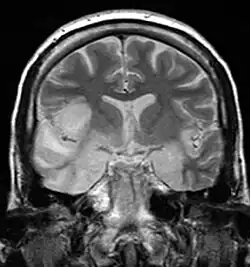

![]() MRI głowy w sekwencji T2-zależnej, w projekcji czołowej, u 33-letniej kobiety z opryszczkowym zapaleniem mózgu | |

Rezonans magnetyczny mózgu pokazuje zmiany u 90% chorych, tomografia komputerowa u ok. 2/3. Elektroencefalografia wykrywa zmiany, ale jest mało specyficzna (32%), czułość metody wynosi 84%.